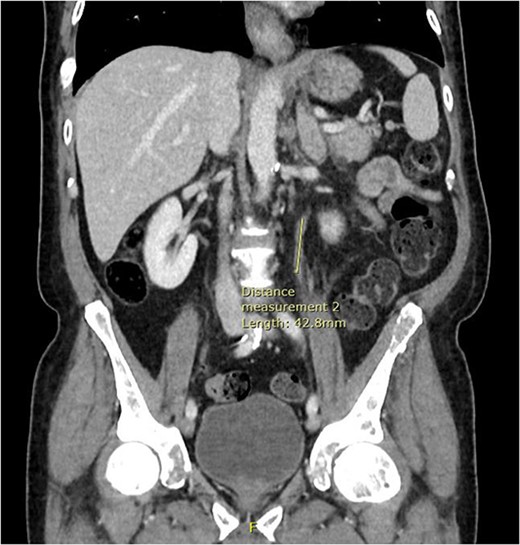

Computed tomography (CT) of the thorax, abdomen and pelvis was requested for staging. Lymphadenopathy was present superior and inferior to the diaphragm, left-sided hydronephrosis with reduced enhancement of the left kidney and widespread mixed lytic and sclerotic lesion affecting the skeleton. The bulky left adrenal gland was concerning for adrenal metastasis (Fig. 3). There was also abnormal urothelial enhancement in the left distal ureter for 4 cm, raising the suspicion of urothelial malignancy (Fig. 4). Blood tests showed a normal prostate specific antigen, mild acute kidney injury, CA19–9 of 17 256 and a carcinoembryonic antigen of 18.

Coronal CT abdomen and pelvis scan with contrast demonstrating urethral enhancement for a distance of 42.8 mm.